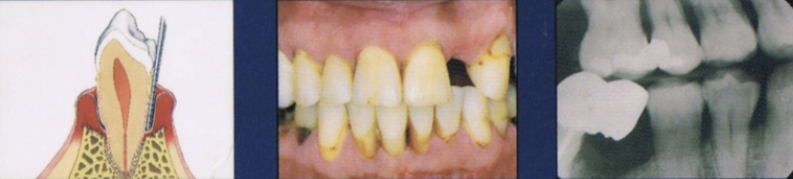

Describe advanced stage of periodontal disease

Major loss of alveolar bone support

increased tooth mobility

Furcation involvement